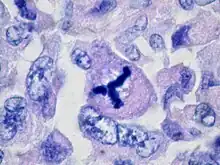

| Metaplastic (sarcomatoid) carcinoma of the breast. | |

Sarcomatoid carcinoma, sometimes referred to as pleomorphic carcinoma,[1] is a relatively uncommon form of cancer whose malignant cells have histological, cytological, or molecular properties of both epithelial tumors ("carcinoma") and mesenchymal tumors ("sarcoma"). It is believed that sarcomatoid carcinomas develop from more common forms of epithelial tumors.[2]